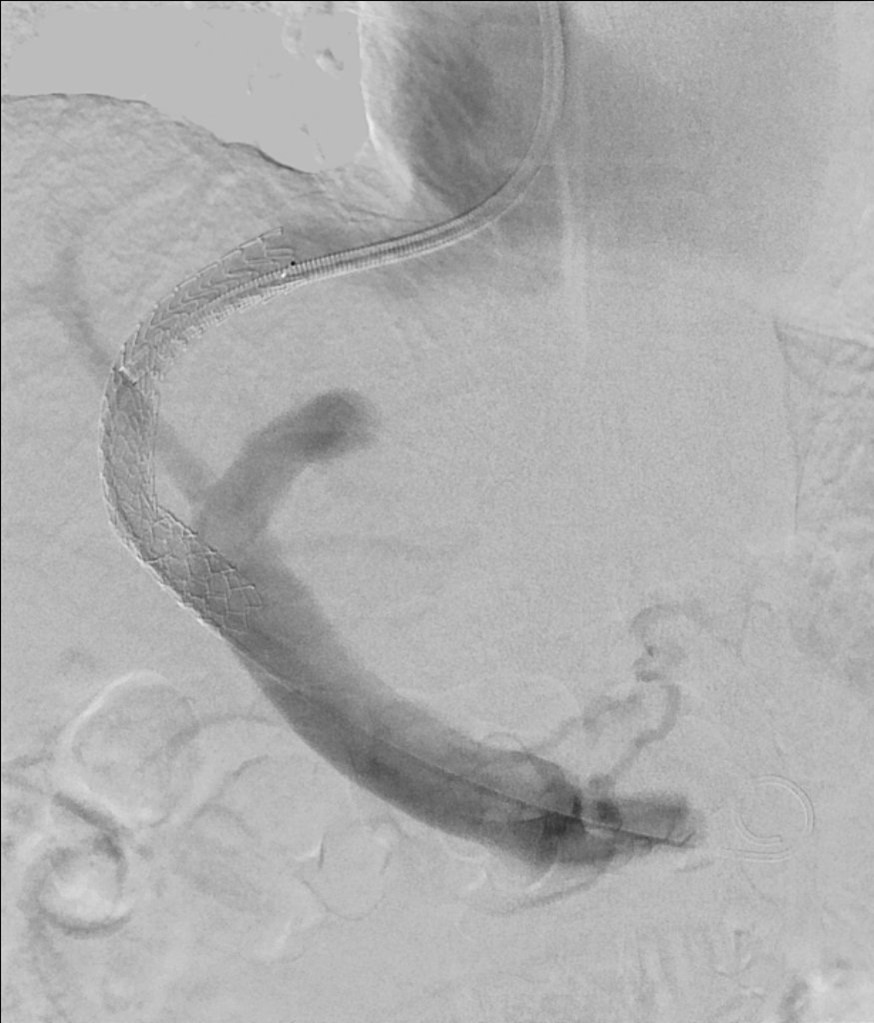

Behandlung des Pfortaderhochdrucks – TIPS-Anlage

Das Vorliegen eines Pfortaderhochdrucks, zum Beispiel in Folge einer Leberzirrhose, kann zu lebensbedrohlichen Komplikationen, wie Blutungen aus Krampfadern der Speiseröhre und dem Magen führen. Zudem gibt es weitere Komplikationen, wie die Ausbildung von Bauchwasser, welche die Lebensqualität der betroffenen Patienten maßgeblich beeinträchtigen können.

Die Anlage eines transjugulären intrahepatischen portosystemischen Shunts (TIPS) ist ein interventionell-radiologisches Verfahren, welches dem Pfortaderhochdruck entgegenwirkt. Hierbei wird über einen kleinen Zugangsweg über eine Halsvene eine künstliche Verbindung zwischen der Pfortader und der Lebervene geschaffen.

Neben der TIPS-Anlage kann es notwendig sein, während derselben Untersuchung größere Umgehungsgefäße beziehungsweise Krampfadern zu verschließen, um das Risiko einer Blutung in Zukunft noch weiter zu reduzieren und den Blutfluss über den neuen Shunt zu verstärken.